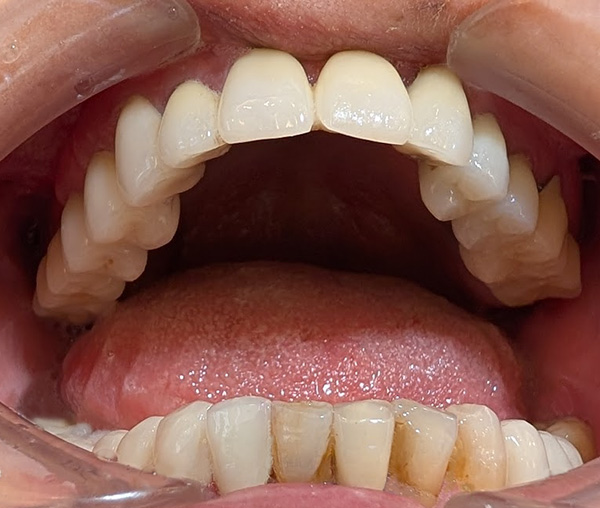

インプラントの長期症例

掲載写真撮影:2025年(75歳/女性)

インプラント:2001年(年前)インプラント埋入 当時51歳